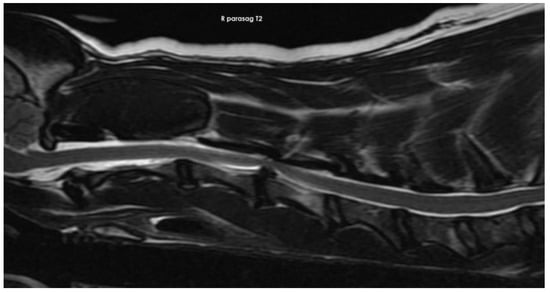

2.1. Imaging Protocols

3.2. Diagnostic Imaging